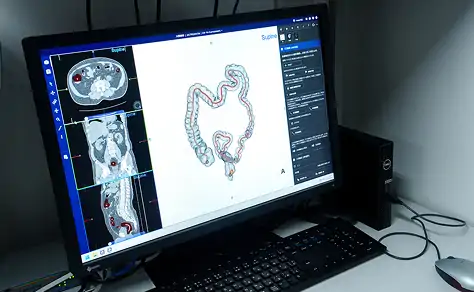

【大放出セール】 Amazon.co.jp: 大腸CTテキスト: 原理・特性の基礎知識から現場で 語学+参考書の詳細情報

Amazon.co.jp: 大腸CTテキスト: 原理・特性の基礎知識から現場で。大腸CT検査~実務・症例・基礎知識~: イチから学ぶ! | 東海。大腸CT検査 | 医療法人 山下病院|愛知県一宮市の消化器内科。 現在、1名がこの商品を検討中です

撮影から読影までを網羅した東芝の大腸CT技術について - 東芝

撮影から読影までを網羅した東芝の大腸CT技術について - 東芝

大腸CTテキスト:原理・特性の基礎知識から現場で使えるセッティング,読影法まで消化管先進画像診断研究会

大腸CTテキスト:原理・特性の基礎知識から現場で使えるセッティング,読影法まで消化管先進画像診断研究会